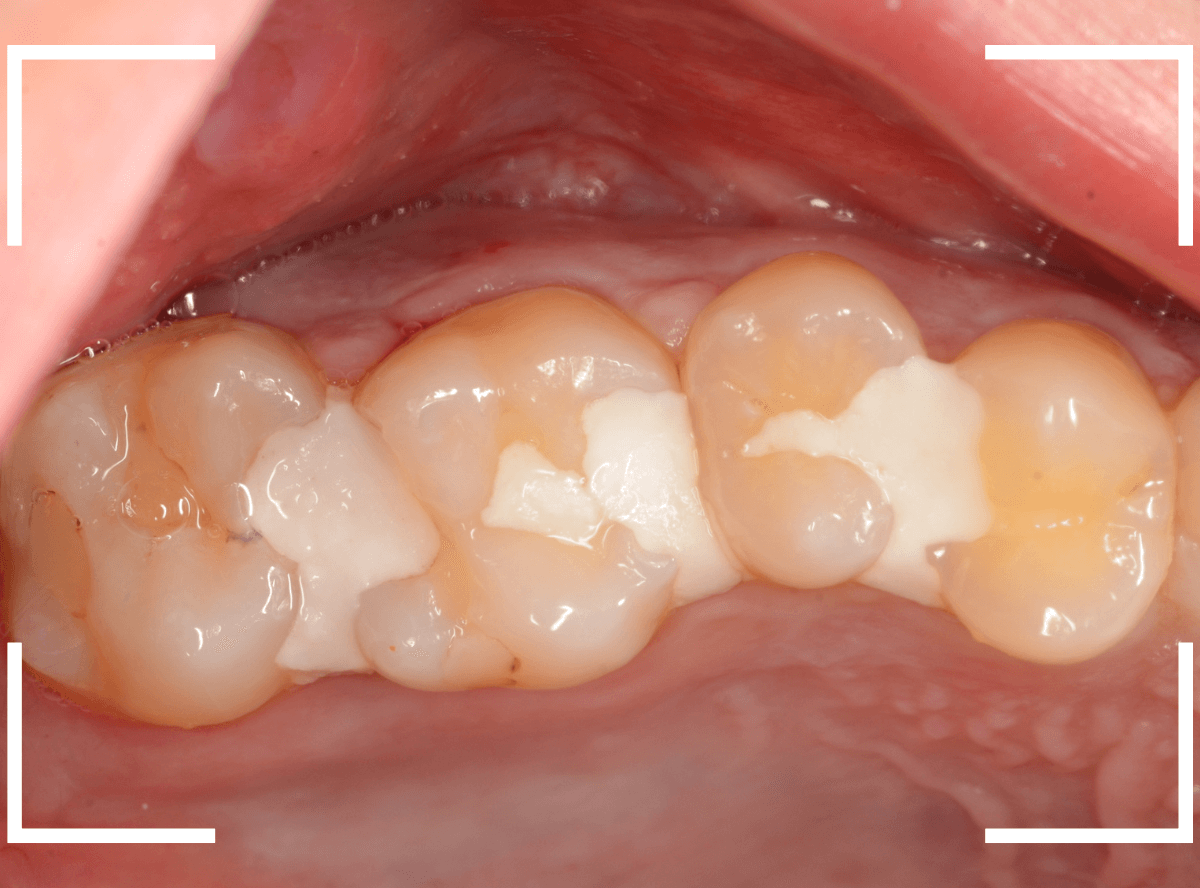

虫歯の治療を開始します。

隣の歯とのすき間を中心に広い虫歯になっていました。

虫歯治療後、特に症状もなく経過観察できましたので、つめものを作る治療に入ります。

セラミック治療をご希望されましたので、

小臼歯をE-MAX・インレー、

大臼歯をジルコニア・インレーで処置することになりました。